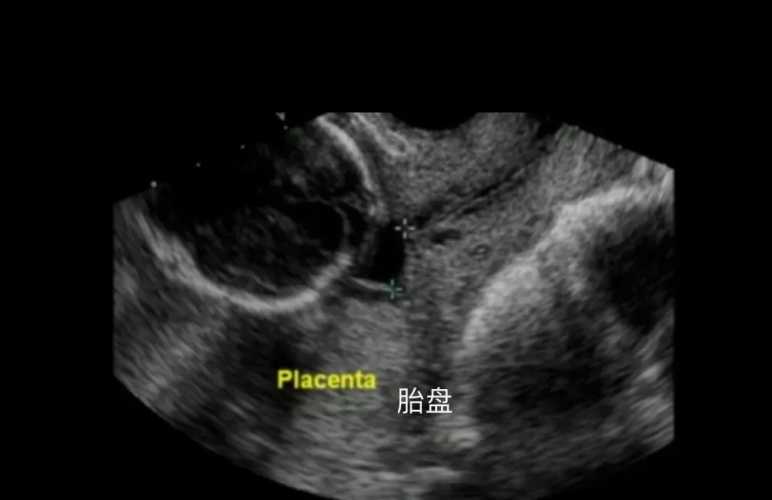

剖腹产胎盘厚是咋回事?这和孕期激素变化、胎盘自身发育还有一些合并情况有关。

孕期激素会影响胎盘生长,有些宝妈身体里激素波动大,胎盘就可能长得厚些。还有胎盘自己发育的情况,比如局部增生也会让胎盘变厚。我之前有个姐妹,产检时发现胎盘厚,后来查是孕期血糖稍微高了点,胎盘为了给宝宝供营养,就跟着增厚了。

不过也别太慌,医生会看胎盘功能、宝宝发育这些情况。要是胎盘厚但功能正常,宝宝也没异常,大多不用太担心;但要是有胎盘早剥这些风险,就得听医生安排啦。